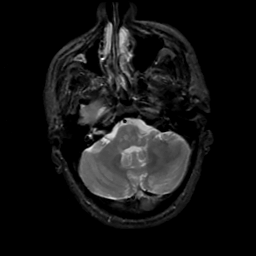

MR Study #5, March 10, 1991 -- Slice #12